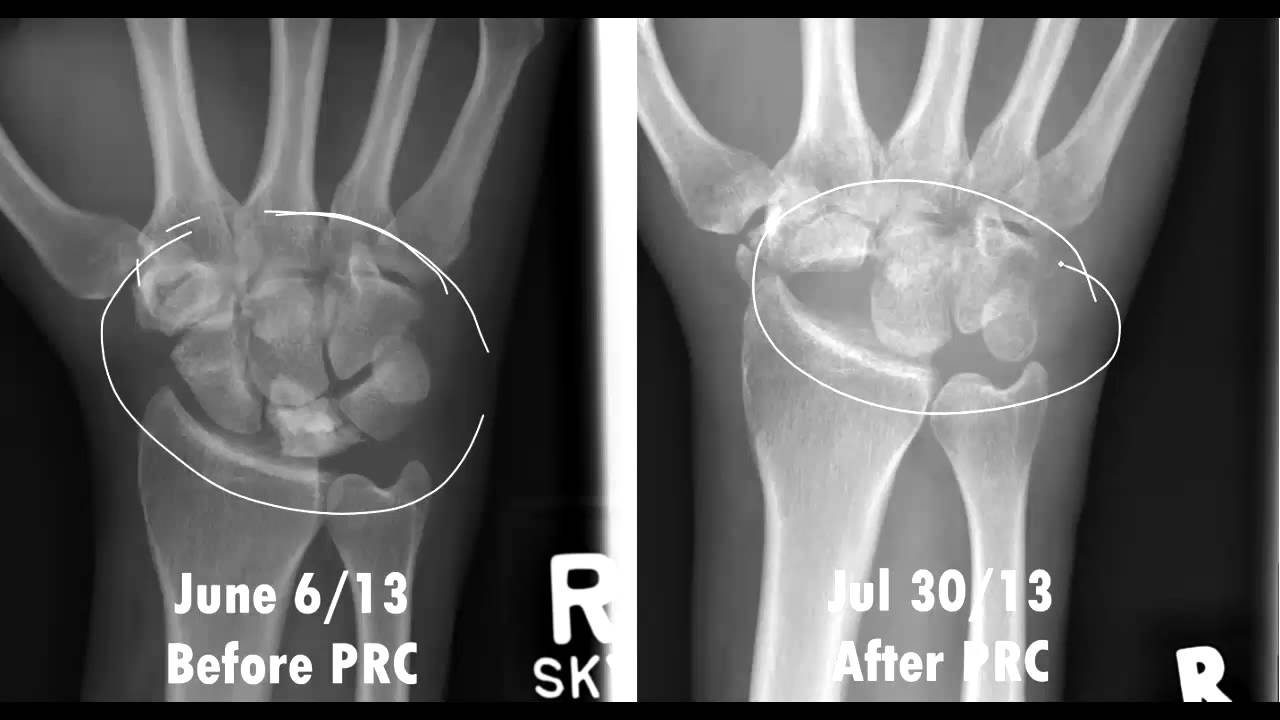

Stage III 부터는 주상골도 영향을 받기 시작하며 회전을 하거나(IIIA, cortical ring 관찰가능), carpal height 가 줄어드는 것을 확인할 수 있습니다. (IIIB), IIIA 까지는 II와 치료를 거의 동일하게 하지만, IIIB 부터는 Proximal row carpectomy 나 STT, SC fusion 등을 시행해 볼 수 있습니다.